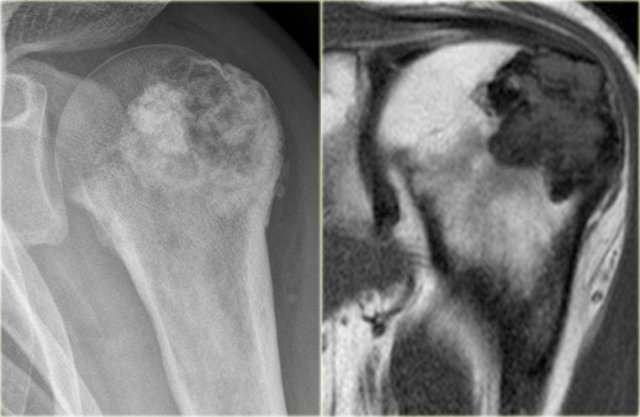

Chondroblastoma in proximal humerus Chondroblastoma in proximal humerus

Chondroblastoma (4)

Here a lesion located in the epi- and metaphysis of the proximal humerus.

The lesion is predominantly calcified.

Coronal T1W image shows lobulated margins and peripheral low SI due to the calcifications.

Notice the surrounding decreased signal intensity of the bone marrow, consistent with edema.

Edema almost always accompanies chondroblastoma, but is unusual in other chondroid tumors, like enchondroma or low-grade chondrosarcoma.

Diagnosis: Chondroblastoma.